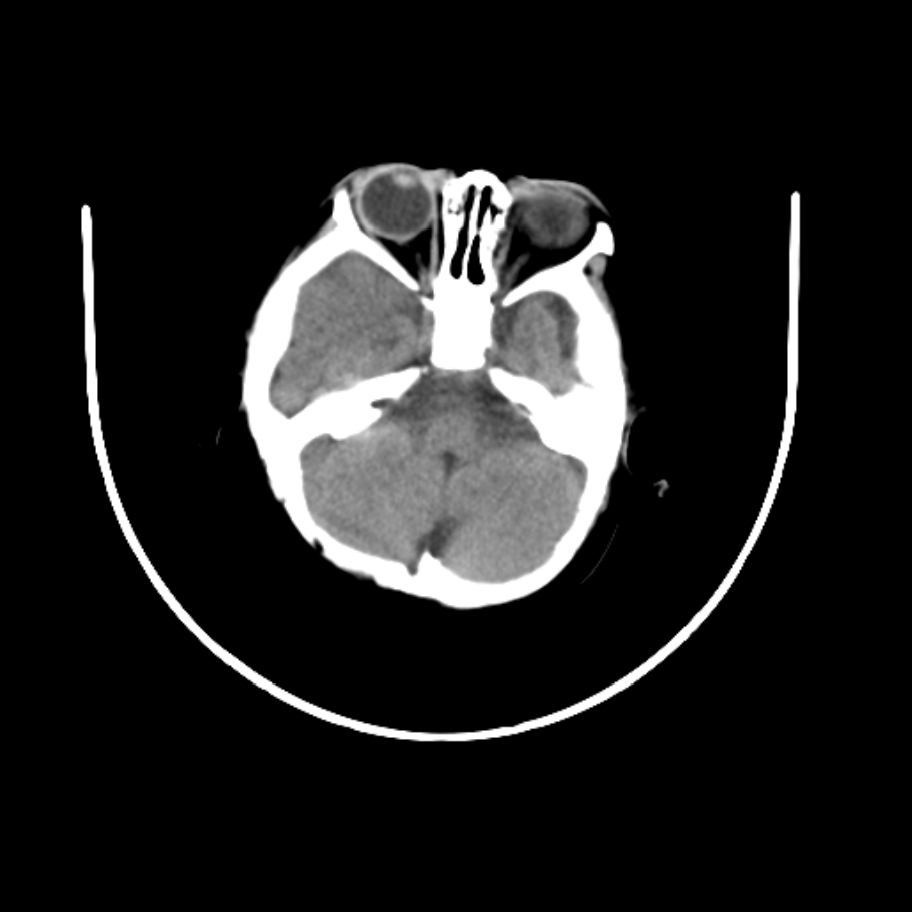

以下是引用随光逐影在2009-4-8 7:51:00的发言:[br]1)透明隔缺如(视-隔发育不良?)。2)右侧脑裂畸形。3)右侧幕上半球脑萎缩。